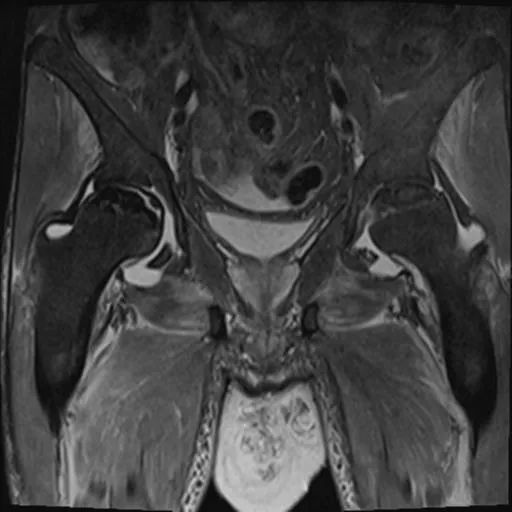

双侧股骨头前上面有大面积的骨髓异常,T1为低信号,在T1和T2W图像上,周围环绕着低强度的边缘。双股骨头呈线性软骨下骨折/断裂,在脂肪抑制图像上得到很好的评价。两侧均有轻度塌陷/扁平的轻微轮廓畸形。这些发现代表了双侧股骨头缺血性坏死。

骶髂关节和耻骨联合正常。

盆腔内存在小体积游离液。弥漫性软组织水肿见于前腹壁及骨盆、大腿。这些发现是由于慢性肾脏疾病造成的。